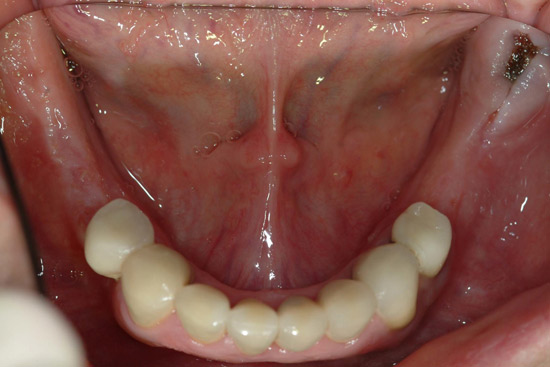

I was lucky – with much support - I commenced a complete dental reconstruction in 2005 - bone grafts, 17 implants and a strong set of gleaming new teeth.